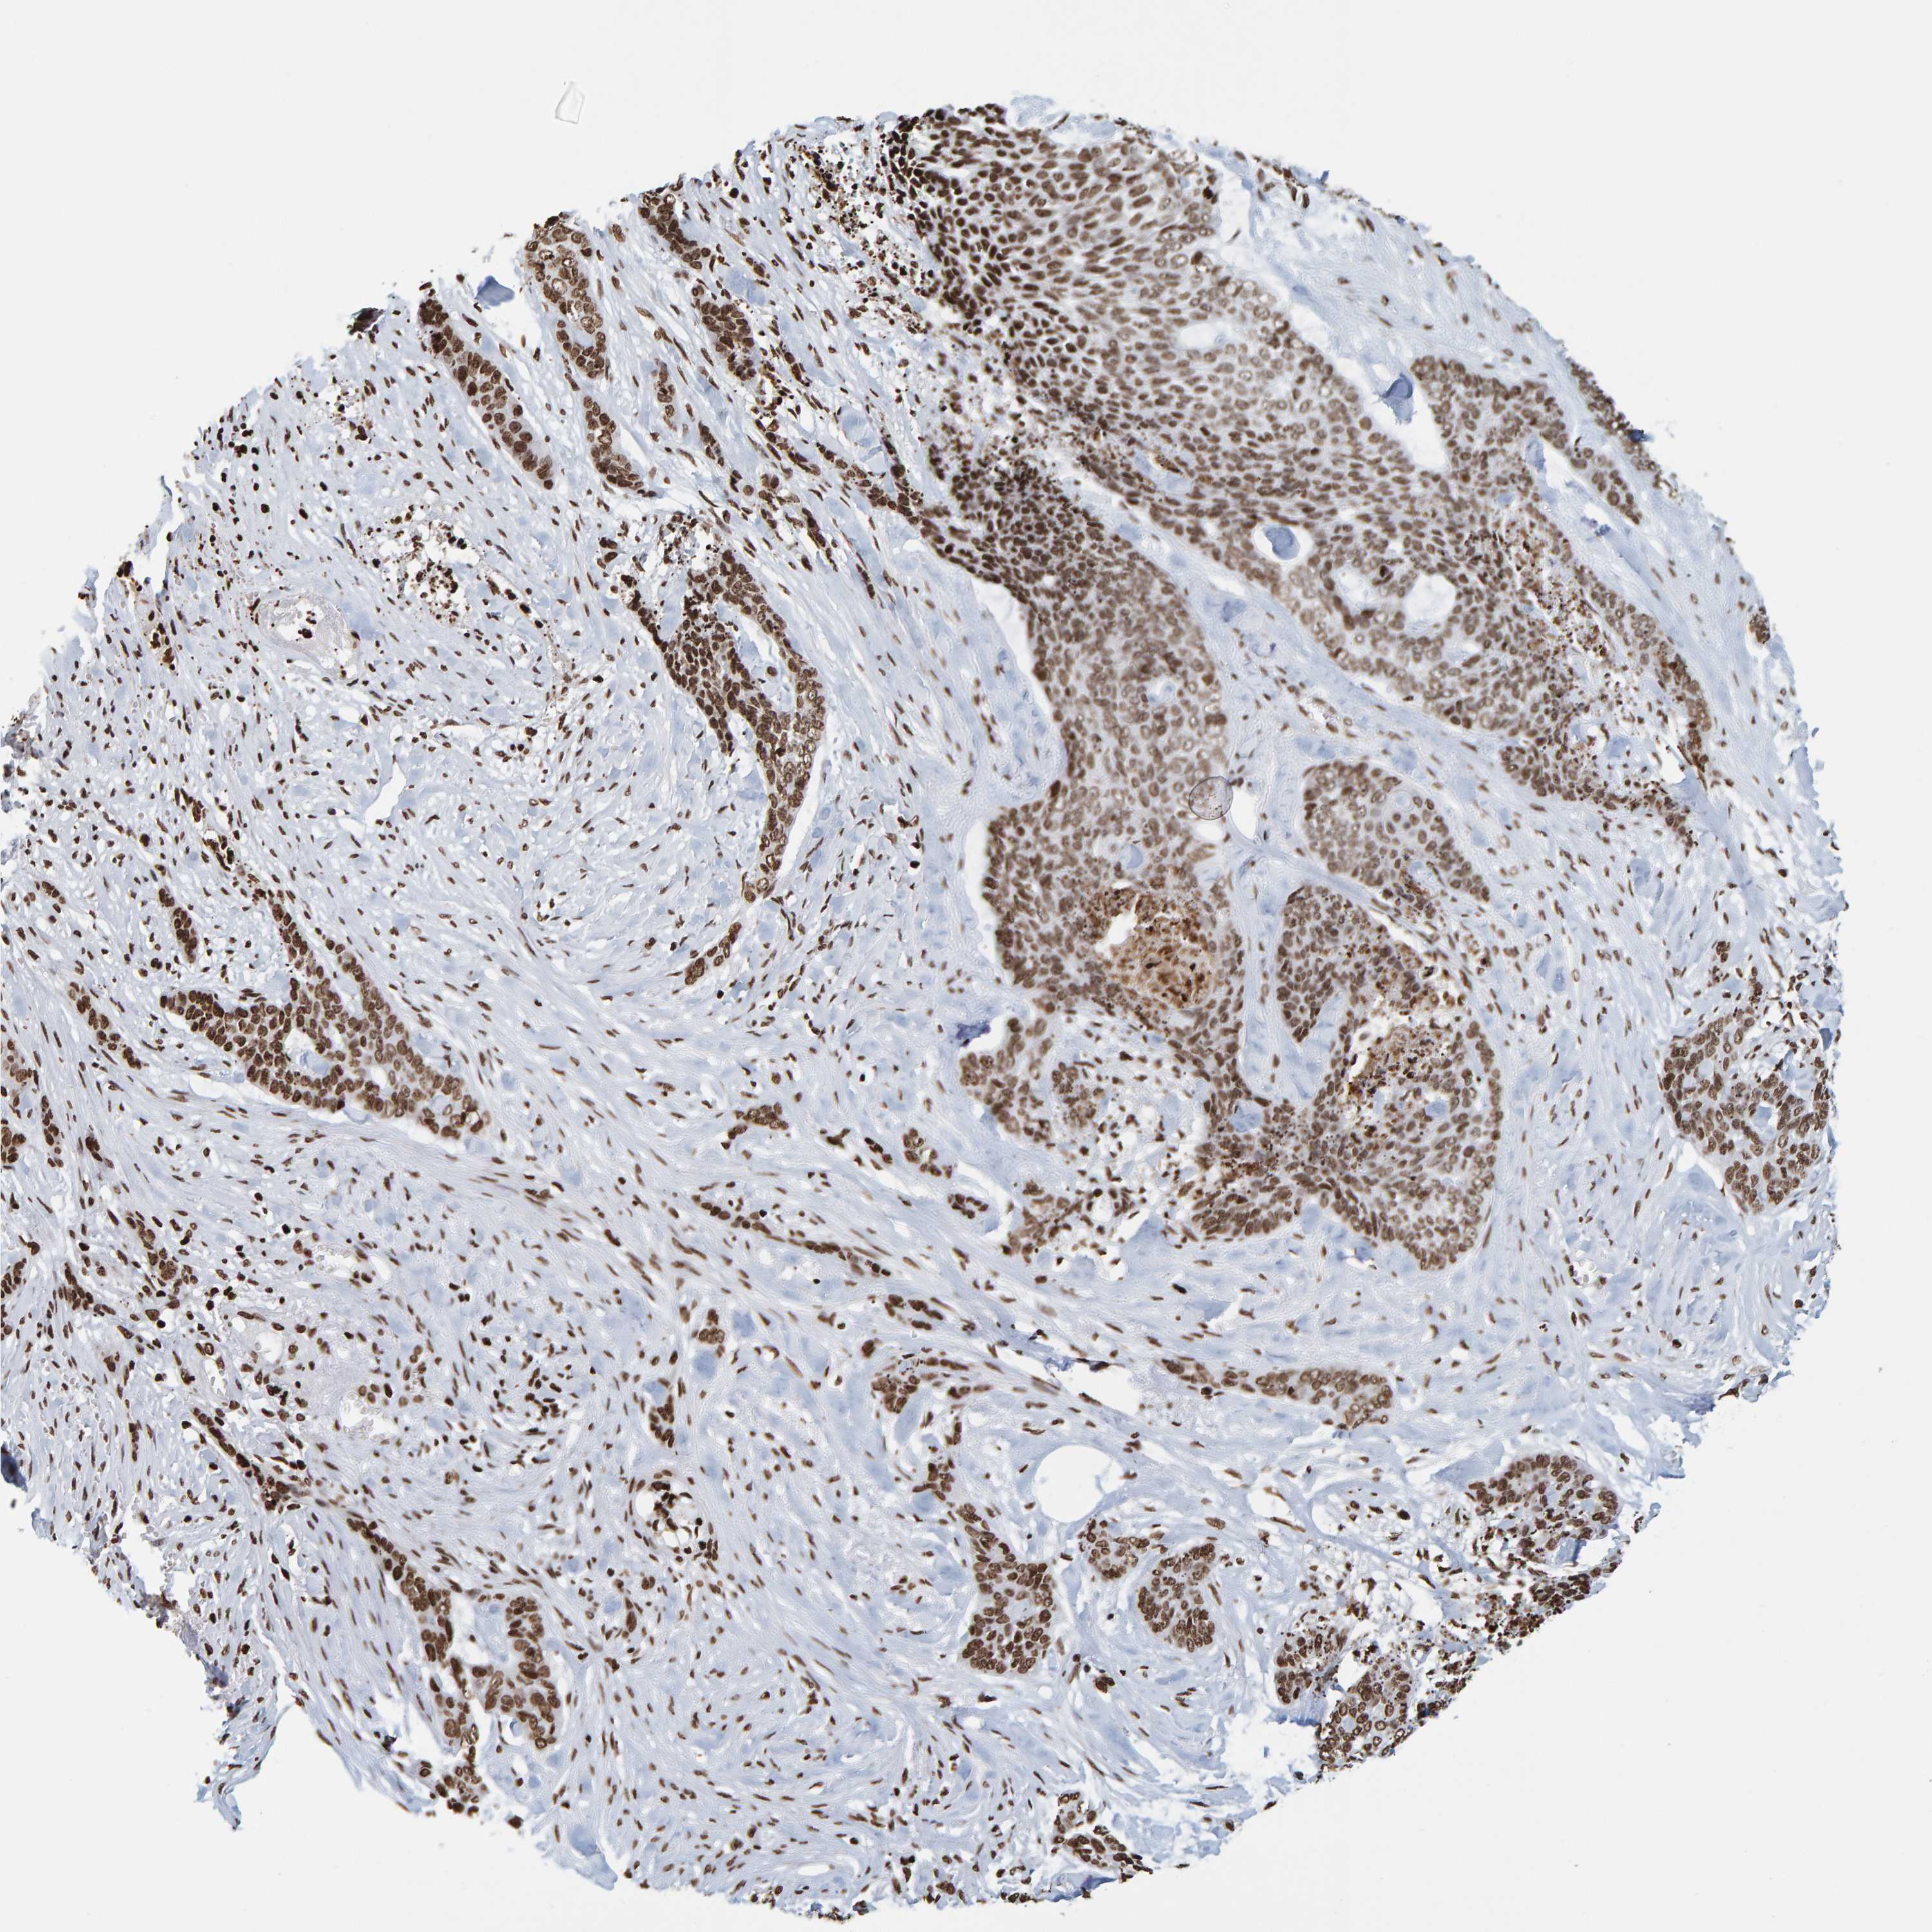

SKIN CANCER - Protein expressioni

A mouse-over function shows sample information and annotation data. Click on an image to view it in a full screen mode. Samples can be filtered based on level of antibody staining by selecting one or several of the following categories: high, medium, low and not detected. The assay and annotation is described here.

Antibody stainingi

Antibody staining in the annotated cell types in the current human tissue is reported as not detected, low, medium, or high, based on conventional immunohistochemistry profiling in selected tissues. This score is based on the combination of the staining intensity and fraction of stained cells.

Each image is clickable and will lead to virtual microscopy that enables deeper exploration of all samples and also displays staining intensity scores, fraction scores and subcellular localization as well as patient and tissue information for each sample.

Antibody CAB019269

Squamous cell carcinoma, metastatic, NOS